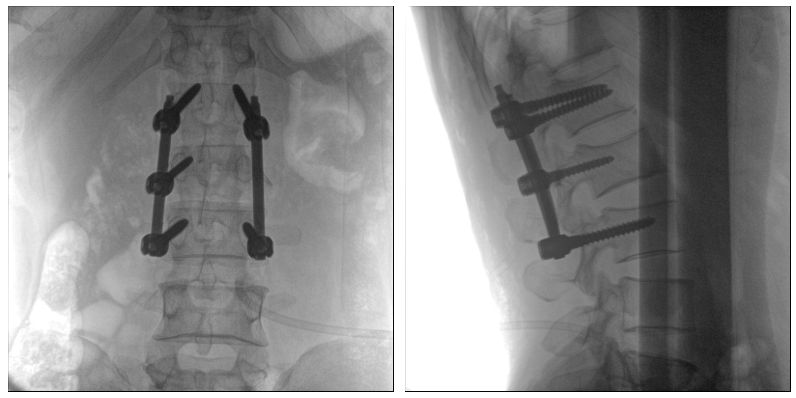

从下图中可以看到二维影像能够提供目标区域在某一个平面的重叠影像,虽然因为人体不同组织的密度差异,使得图像具有较为丰富的信息量,但组织间的相互重叠还是会出现,诸如空间位置等众多信息在影像中遗失或不可辨认的情况,影响了医生对信息的收集与应用。

术中二维影像